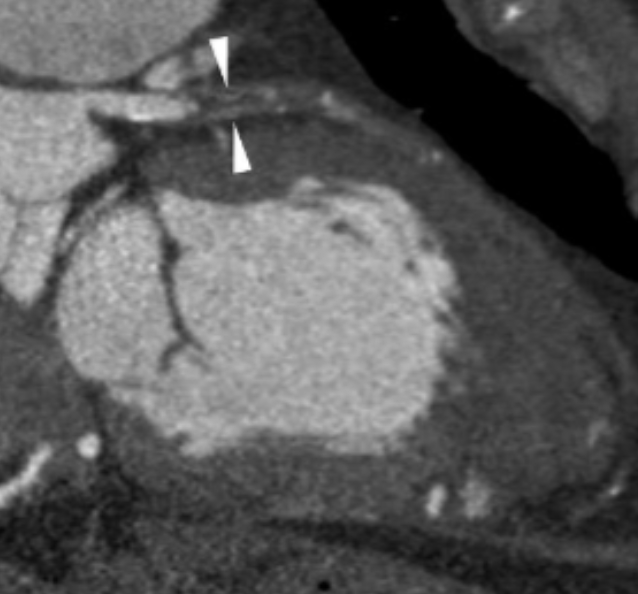

Describe the CT scan protocol/view:

Oblique MIP of the RCA

Describe the RCA findings in this image:

Cardiac Motion Artifact